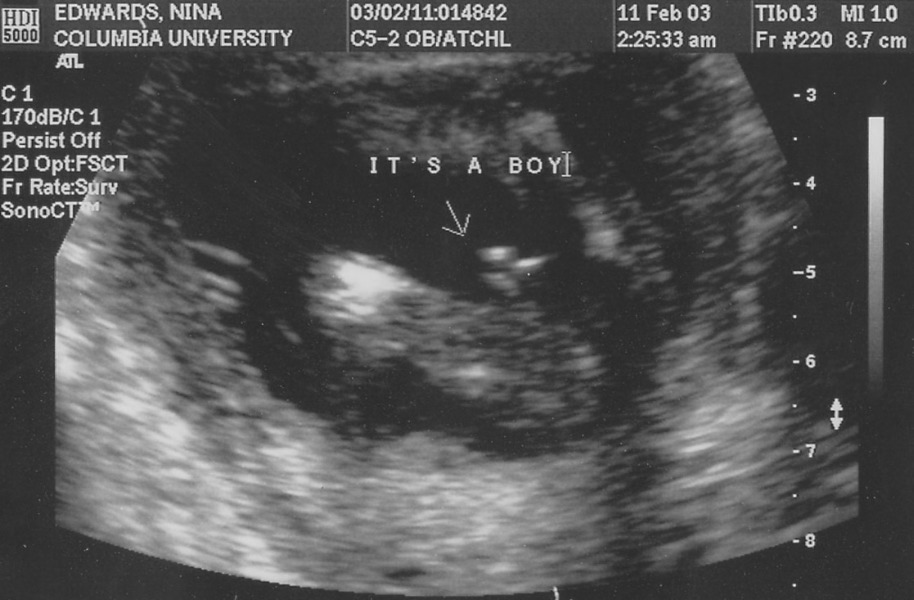

p2030001 Its A Boy Ultrasound

Nina was disappointed it wasn't bigger.